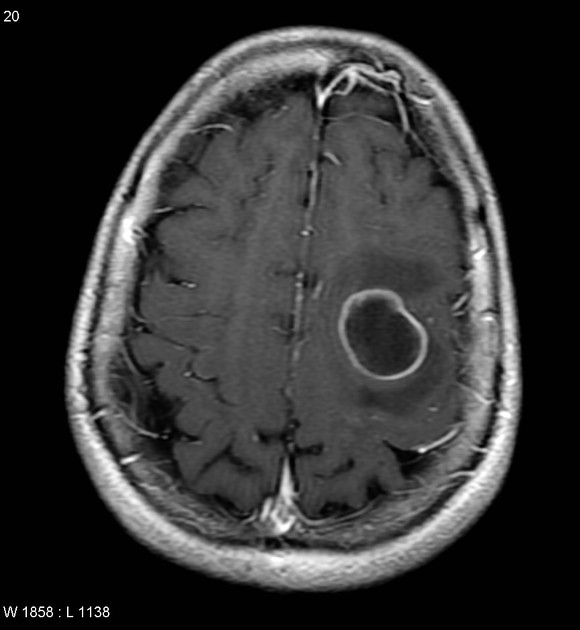

A 42-year-old man is brought to the physician 25 minutes after an episode of violent jerky movements of his hands and legs that lasted for 5 minutes. After the episode, he had difficulty conversing. For the past 10 days, he has had a left-sided headache and nausea. Apart from a history of recurrent ear infections treated with antibiotics, he reports no other personal or family history of serious illness. He works as an assistant at a veterinarian clinic. He appears ill and is oriented to place and person only. His temperature is 37.8°C (100°F), pulse is 102/min, and blood pressure 112/78 mm Hg. Examination shows bilateral optic disc swelling. There is no lymphadenopathy. Muscle strength and tone is normal in all extremities. Deep tendon reflexes are 2+ bilaterally. Plantar reflex shows a flexor response bilaterally. Laboratory studies show a CD4 count within the reference range. An MRI of the brain is shown. Intravenous mannitol and levetiracetam are administered. Which of the following is the most appropriate next step in management?